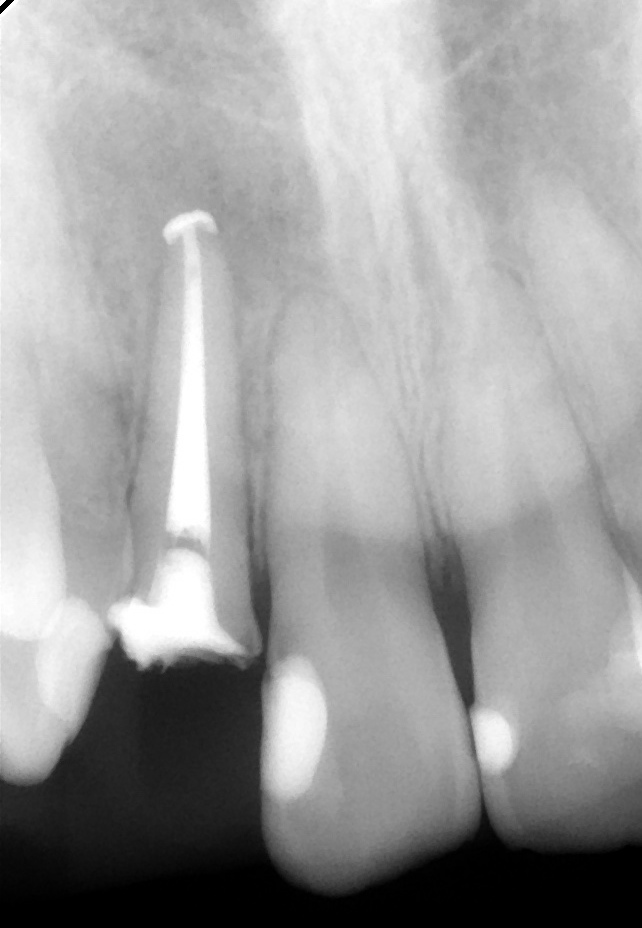

残念ながら日本においては、根の治療の不備によって

レントゲンでは黒い影として歯根の先に見られます。ひどくなるとズキズキ痛んだり、ぱんぱんに

腫れてしまったり、膿みがでてきたりします。とにかく急性期には堪え難い状態になりますが、

慢性期はそんなにでもありません。しかしこれを繰り返しているうちに、顎の骨が溶けていって

しまいます。

しかし適切に根管治療を行えば、根尖病巣を治癒に導くことも充分可能です。